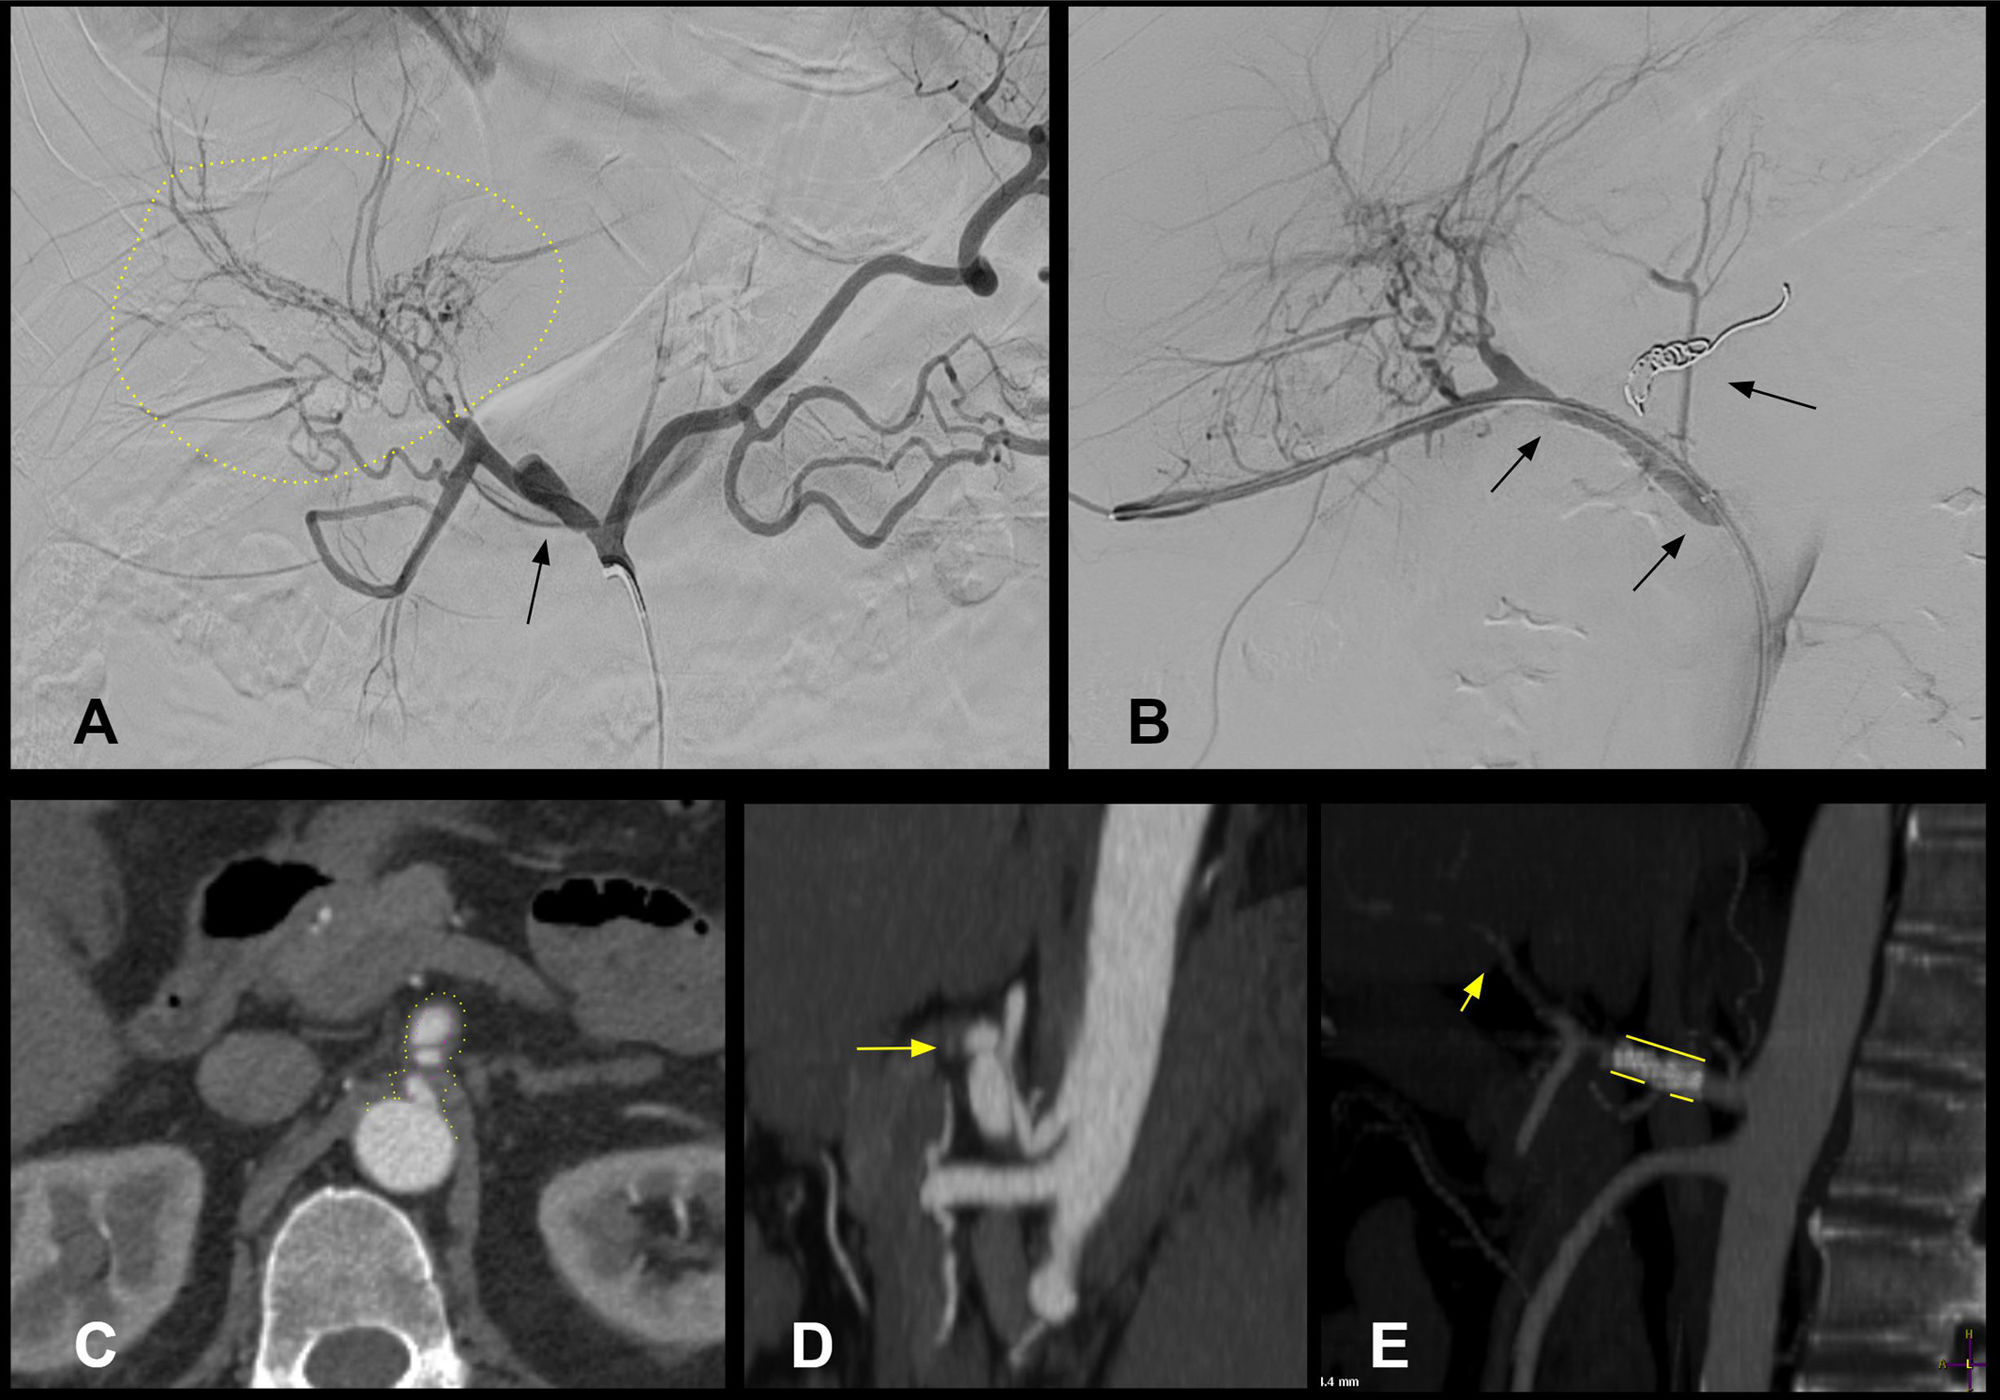

Segmental arterial mediolysis (SAM) and fibromuscular dysplasia (FMD) are rare vasculopathies. Differentiating between them is difficult due to its similarities. The aim is to describe and compare the clinical characteristics, presenting symptoms, diagnostic tests, treatment, and outcomes.

ResultsFour patients with SAM and 18 with FMD were included. SAM predominated in males with abdominal pain (75%), while FMD in young women (61.1%) with neurological manifestations (66.6%). Anticoagulation was the main treatment for SAM, and antiplatelet therapy for FMD. Surgical treatment was performed in 25% and 22.2%, while percutaneous intervention was performed in none and 27.7% of patient, respectively. During follow-up (median 3.4 years), mortality was similar in both groups (10%).

ConclusionThere are key differences in clinical presentation, management, and outcomes that may help guide the treatment of both conditions.